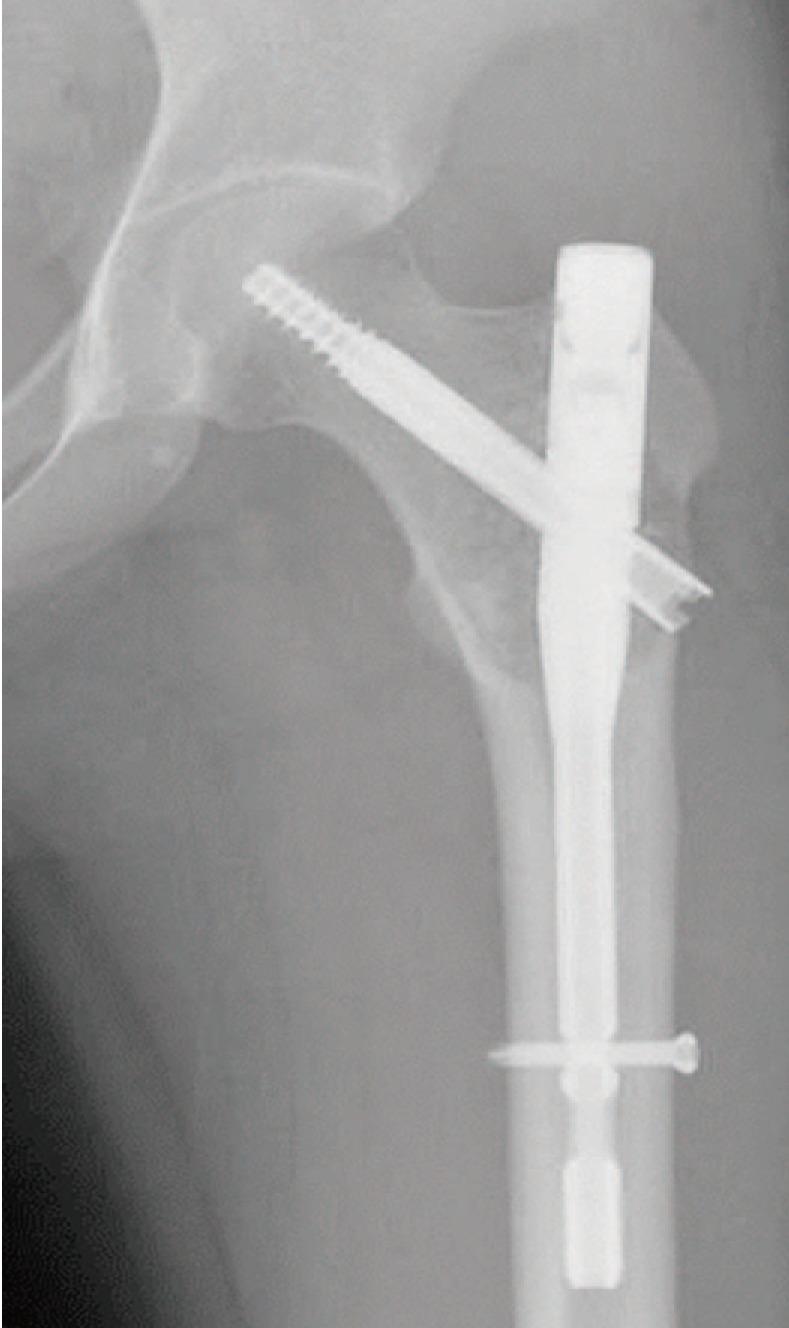

We report the case of a 25-year-old woman presenting with left hip pain. A lesion was found in the proximal femoral metaphysis. Benign bone tumor, such as intraosseous lipoma or liposclerosing myxofibrous tumor, was suspected based on simple radiographs and magnetic resonance images. Curettage of the lesion and bone grafting was performed. Histologic findings reflected primary intraosseous xanthoma of the proximal femur. Laboratory tests revealed the patient to be normolipidemic, while immunoelectrophoretic fractionation of lipoproteins revealed normal values for alpha, pre-beta, beta, and chylomicrons. At the one-year follow-up, there was no evidence of local recurrence. This is the first reported case of primary intraosseous xanthoma of the proximal femur in a normolipidemic patient.

我们报告了一例25岁女性因左髋部疼痛就诊的病例。在股骨近端干骺端发现一个病灶。基于普通X线片和磁共振成像,怀疑为良性骨肿瘤,如骨内脂肪瘤或脂肪硬化性黏液纤维瘤。对病灶进行了刮除和植骨。组织学检查结果显示为股骨近端原发性骨内黄瘤。实验室检查显示患者血脂正常,而脂蛋白免疫电泳分离显示α、前β、β和乳糜微粒值正常。在一年的随访中,没有局部复发的迹象。这是首例血脂正常患者的股骨近端原发性骨内黄瘤报告病例。